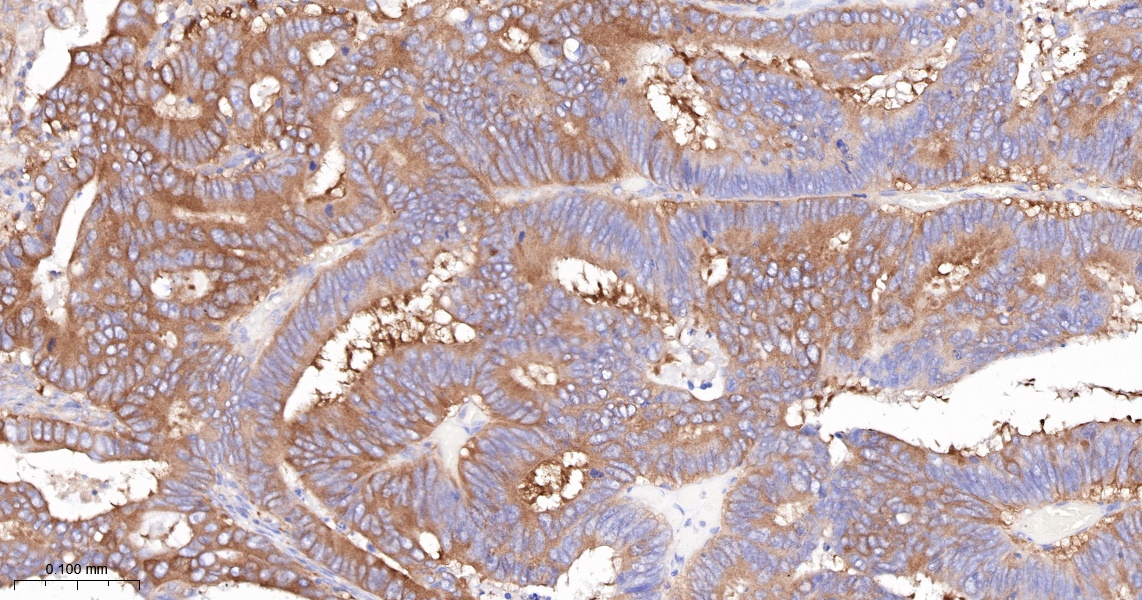

IHC-P IHC-P1:100-500